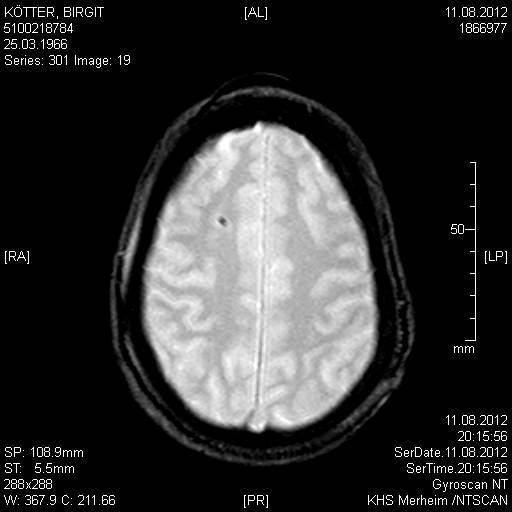

Das ist das Aneurysma:

image9

In den Aufnahmen vom 11.08.2012 sind noch eindeutig die Gehirnstrukturen zu erkennen:

image11